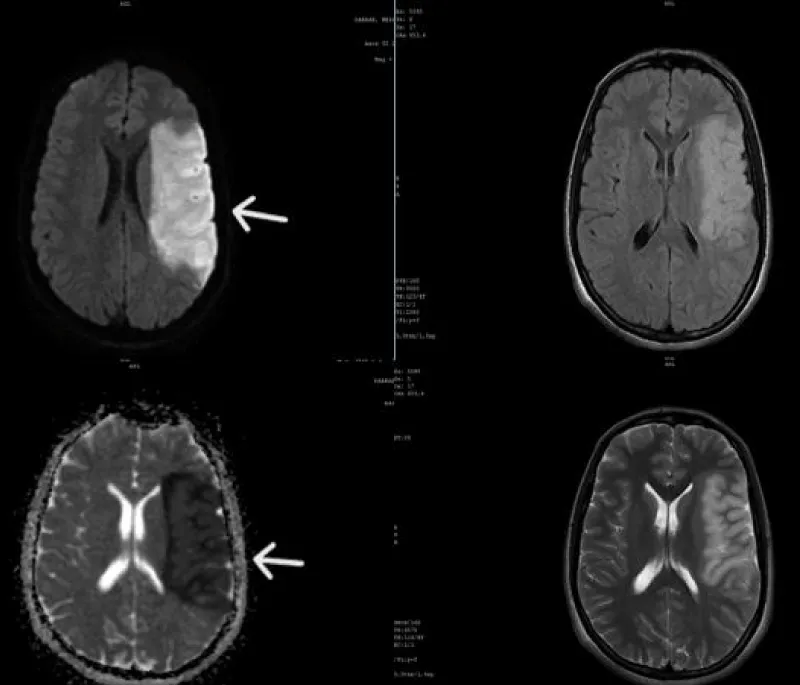

An urgent brain MRI was performed, revealing an extensive area of ischemia in the left middle cerebral artery territory with mass effect but no signs of hemorrhagic infarction (Figure 2).

Figure 2: Brain MRI showing a left deep Middle Cerebral Artery (MCA) stroke (white arrow), with an extensive ischemic lesion, noticeable mass effect, and no signs of hemorrhagic transformation.

Imaging modalities play a crucial role in identifying neurological and cardiac involvement in patients with Behçet’s disease, guiding diagnosis, and assessing the severity of lesions. Brain MRI is essential in diagnosing ischemic stroke associated with Behçet’s disease, allowing visualization of ischemic areas and identification of vascular lesions in the deep brain structures, which are frequently affected in this condition.